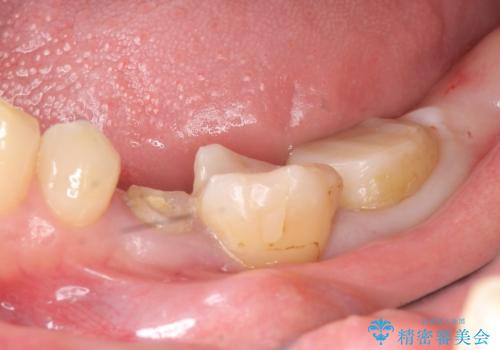

- 左下の奥歯がズキズキ痛むので診て欲しいといらっしゃった方の症例です。他院では5番目と7番目の歯を抜歯してインプラントと言われたが、出来れば歯を残したいとのことでした。

痛みの原因は6番目の虫歯であること、5番目、6番目の歯は歯茎より深い虫歯であり現状では保存が難しいことを説明した上で、歯を挺出させる部分矯正と歯茎を下げる歯周外科を行いました。

虫歯が進み歯茎より深くなってしまうと、虫歯を取り残してしまうリスク、樹脂の硬化の妨げ、補綴物の不適合、歯肉炎・歯周病のリスクの増大等様々な弊害が起こり得ます。